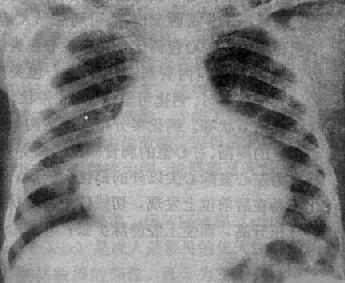

X线表现(图3-2-16),二尖瓣回流较轻,心代偿功能良好时,心大小和形状无明显改变,仅见左心房和左心室轻度增大,当二尖瓣回流在中度以上,心肌代偿功能较差时,则左心房明显增大,在心室也增大,透视下可见左心室收缩时因瓣膜关闭不全而左心房有强烈的搏动。肺有瘀血,右心室亦可增大。主动脉球正常或略小。

图3-2-16 二尖瓣关闭不全并狭窄

心增大呈二尖瓣型,右心室增大,肺动脉

段突出,左心耳增大,有肺瘀血